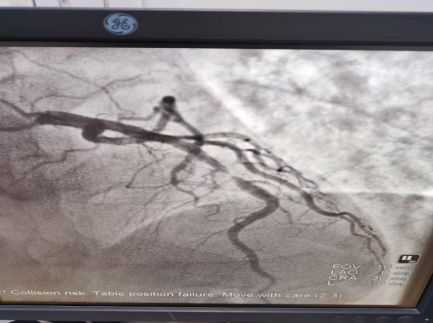

根據(jù)冠脈造影結(jié)果,康振興主任考慮血管病變局限,鈣化不明顯并且無扭曲,向家屬告知病情,決定置入生物可降解支架,置入后血管完全通暢(圖二),透視情況下僅可見支架標(biāo)記點(diǎn)(圖三),術(shù)后恢復(fù)良好,目前患者康復(fù)出院。

圖二                           圖三